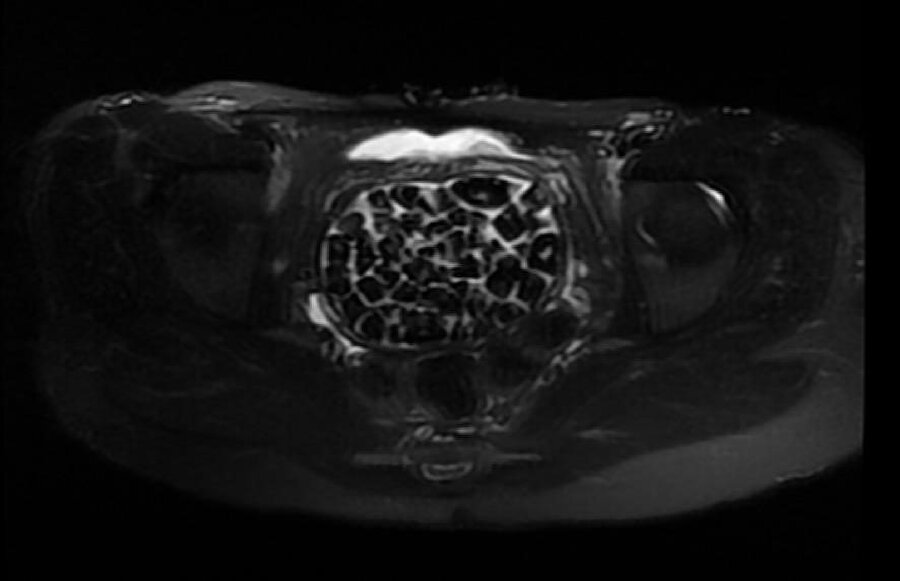

Hastasının durumuna yönelik konuşan Üroloji Uzmanı Doç. Dr. Erkan Erkan, "Hastamızın 2004 yılında doğduğunu ardından doğar doğmaz ekstrofi vezika dediğimiz 50 binde bir görülen bir anomaliden dolayı art arda ameliyatlar geçirdiğini öğrendik. 10 yaşında yine bir ameliyat geçirmişti, gerekli görüntüleme ve tetkiklerimizi yaptırdık. Normalde mesanesinin olması gereken yerin hemen arka kısmında taşlarla dolu bir kese olduğunu gördük, bunun üzerine ek görüntülemeler; MR çektirdik. Hastamız çelişkili açıklamalar almıştı, kendi radyolojik kliniğimiz ve edindiğimiz konsültasyonlarda taşların mesanede değil vajinal boşlukta oluştuğunu düşündük, bir planlama yaptık. Kadın doğum hocamızın da çabasıyla taşları tamamen temizledik ardından ileride normal bir hayat sürmesi bakımından oraya plastik cerrahi yaptık. 287 adet taş çıkardık, pratikte gerçekten görünce çok şaşırdık çünkü bu aynı zamanda literatürde çok nadir görülen bir olay. Biz ameliyata hazırlanırken de teorik olarak biraz araştırdık. Literatürde gördüğümüz kadarıyla buna benzer bu tanıma uyan bir vaka vardı. Literatürde sanırım yayınlanmış 2’nci vaka olacak. Farkındalık çok önemli, bilinçli bir hastamız vardı. Doğumsal anomaliyle doğan çocuklarımızda ileride bunlara bağlı bazı sıkıntılar çıkabileceğinin öngörülmesi lazım. İlgili tedavilerini alsalar bile düzenli takiplere gelmeleri gerekiyor. İleride eğer dikkat etmezse ki zannetmiyorum, tekrarlayabilir. Bu rahatsızlık ekstrofi vezikal epispadias durumu çok nadir bir durum" dedi.

Karnı adeta taşlarla doluydu

Genç kızın uzun süredir devam eden karın ağrısı olduğunu söyleyerek sözlerine başlayan Jinekolojik Onkoloji Uzmanı Op. Dr. Emin Erhan Dönmez, "Mesane taşları olduğu düşünülerek daha büyük bir hastaneye refere edilmiş. Aramızda mini bir konsey yaparak muayene ettik. Vajen bir hazne görevi görerek orada durağan bir idrar, uzun süre beklediği için idrar içindeki minerallerde çökerek taşlar oluşmuş. Mesanedeki idrarın vajene akmış olabileceği ve vajende göllenen idrar nedeniyle taşların burada oluşacağını düşündük, ameliyatımızı planladık. Ameliyata tanı amaçlı girmiştik, sistoskopi (Mesane gibi idrar yollarını kapsayan kısımlardaki rahatsızlıkların teşhis ve tedavisinde kullanılan endoskopik bir yöntem) dediğimiz ameliyatı Erkan Hocam ile birlikte gerçekleştirdik. Önce mesaneyi bir görüntüledik, mesane tabanına yaklaşık 2-3 cm’lik bir alandan vajene fistülize olduğunu gördük. Mesaneden vajene geçtiğimiz esnada tüm vajenin taşlarla dolu olduğunu gördük. Tanı amacıyla girdiğimiz ameliyatta her şey de olağan gittiği için tedaviye geçtik. Taşların çıkabileceği kadar bir genişlik sağladık. Daha sonra yaklaşık en büyüğü 2,5 cm boyutlarında olan, irili ufaklı 287 tane taşı ameliyat esnasında çıkarmış olduk. Taşların tekrarlamaması için idrarın göllenmemesi, en azından dışarıya rahatça boşalabilmesi için vajinal rekonstrüksiyonu sağladık. Ameliyatta da herhangi bir problem yaşamadık. Literatürü Erkan Hocam ile birlikte değerlendirmiştik. Primer olarak vajende birikmiş olan bu kadar çok sayıda taşla ilgili bir makale görmedik, rastlamadık" dedi.